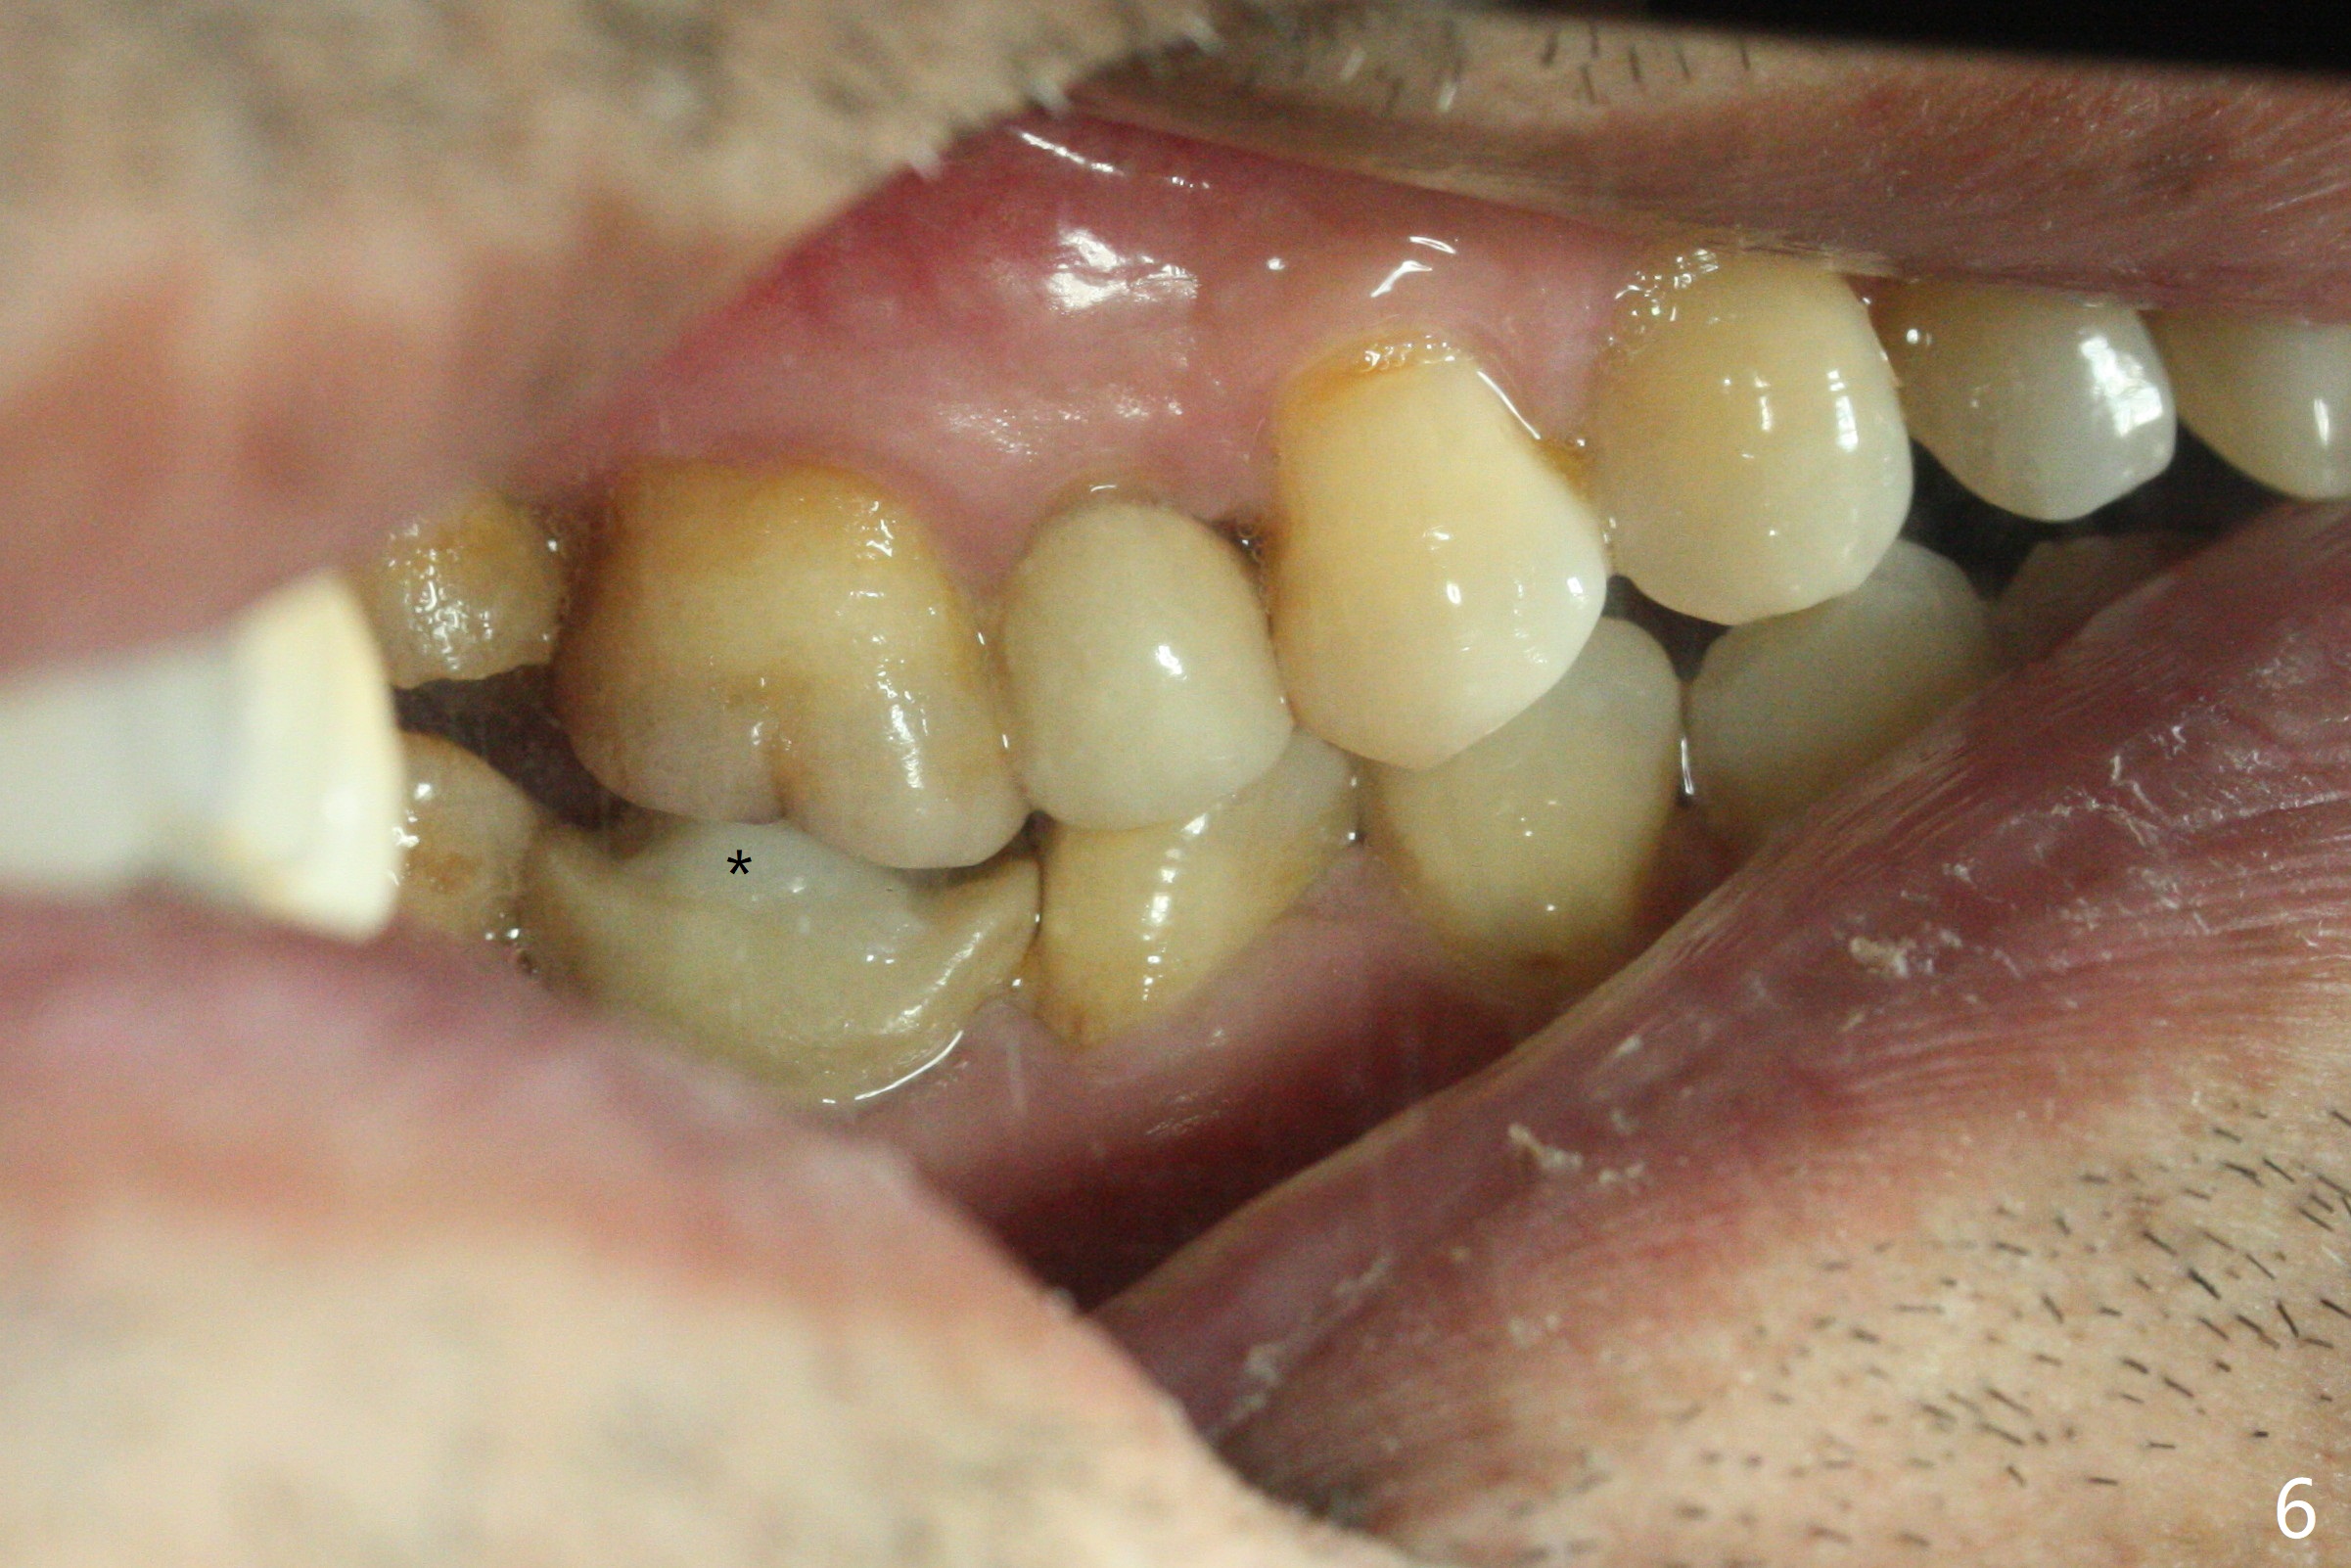

A 62-year-old man complains of food impaction around #19 implant crown one year 4 months post cementation (Fig.1-3). Before redo of the crown with poor mesial emergency profile (Fig.3 *), it appears necessary to correct the supraerupted opposing molar (Fig.1-3 downward arrow) and mesially tilted 2nd molar (Fig.3 horizontal arrow). The tooth #19 had been missing 20 years before implantation, associated with occlusal wear at #18 (Fig.4). For intrusion, composite is placed in the occlusal surface of #19 crown after roughening (Fig.5,6) with occlusal separation of the remaining dentition (Fig.6). The patient is instructed to bite on the left side as much and long as possible (even when he does not eat). Will the tooth #14 be intruded? Is the treatment sufficient?